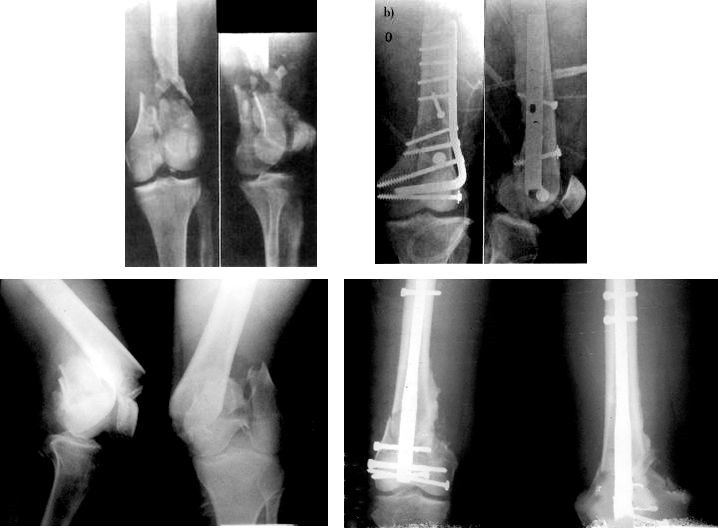

Пациентам с тяжелыми повреждениями мягких тканей, открытыми переломами или трудностями в начале операции - надсуставной аппарат внешней фиксации.

Неотложная хирургическая обработка изолированного повреждения — ДКС, ретроградный интрамедуллярный стержень.

Общее состояние больного стабильное, если позволяют местные кожные покровы, операцию следует проводить немедленно.

Определить характер травмы насилием

Высокоэнергетическая травма часто сопровождается тяжелым повреждением мягких тканей.Он характеризуется отеком конечностей, образованием волдырей, ссадин и разрывов кожи.Операцию следует отложить на это время.При этом необходимо исключить синдром фасциального пространства и повреждения сосудов и нервов.